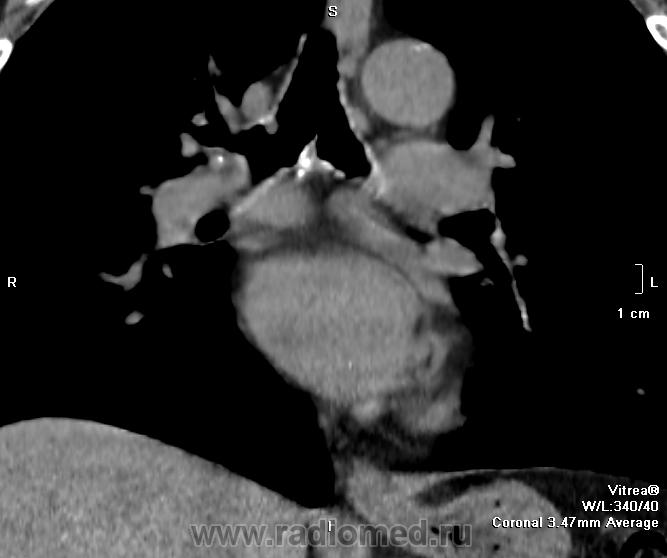

теперь, когда коллеги высказали свое мнение и думать стало легче-), спрошу лишь одно по предложенному мной скану - что за циркулярный гитперденсный обхват трахеи (на всех аксиалах)? почему "на ножке"-то?

имеющее обсуждение образование одно в области правого главного бронха.. явственно эндобронхиального происхождения.. но что мешает придраться к аксиальным срезам с перитрахеальной ненормальной плотностью?..

Вношу ясность: тут два исследования - первое исследование сделано в понедельник, второе во вторник - в просвете бронха имеет место что то симулирующее tr, что было на верхней стенке, а затем переместилось на нижнюю за сутки - слизь.